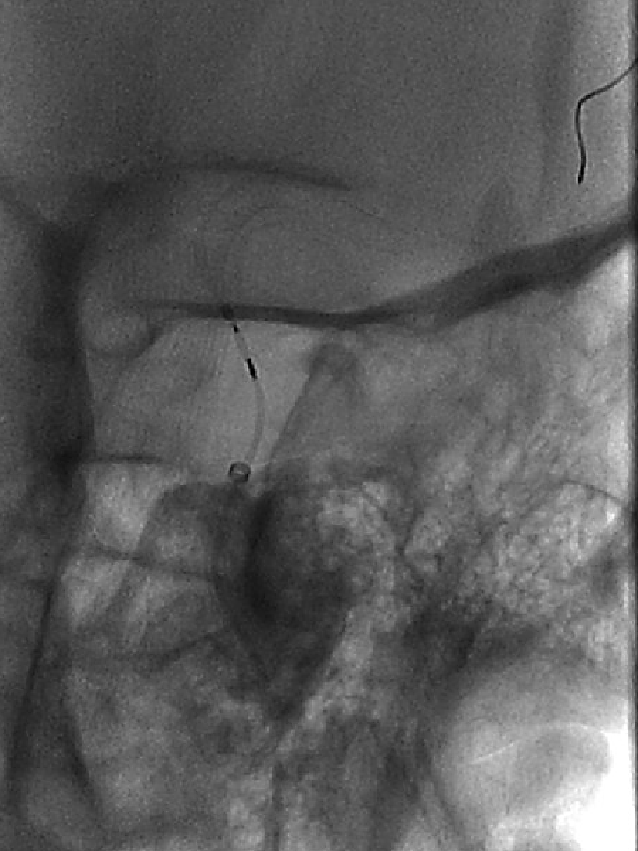

术后图像显示支架打开及贴壁良好。

术后工作位造影

术后侧位造影

术后正位造影

术后患者一般情况可,诉头疼,给予对症处理。神经查体:无阳性定位体征。给低分子肝素4100U皮下注射一次。继续口服阿司匹林100mg 1次/日,替格瑞洛90mg 2次/日。